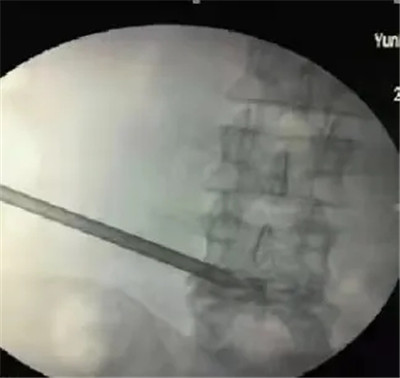

3月12日,由姚安县中医医院骨伤科李林主任领衔的微创治疗团队成功实施了一例椎间孔镜手术。骨伤科顺利完成椎间孔镜手术,标志着我院治疗椎间盘疾患的技术又踏上了一个新台阶,也标志着我院骨伤科在脊柱手术方面又多了一张王牌。

患者杨某宏,腰痛伴右下肢麻木疼痛已有半年,近日疼痛加重,几乎无法正常行走,经医院检查确证为“L5/S1椎间盘突出症”。在患者本人无意愿开放手术的前提下,进一步完善相关影像检查及评估后,符合椎间孔镜下髓核摘除术指征。术前,李林主任团队认真讨论病例,制定了详细的手术方案。3月12日在气管插管全麻下,通过皮肤表面约7毫米的切口,行后路腰椎间盘镜椎间盘髓核摘除术,术后患者腰腿疼痛症状明显缓解,术后第二天即可下床活动,患者于3月17日顺利出院。患者恢复良好,对手术效果表示非常满意。